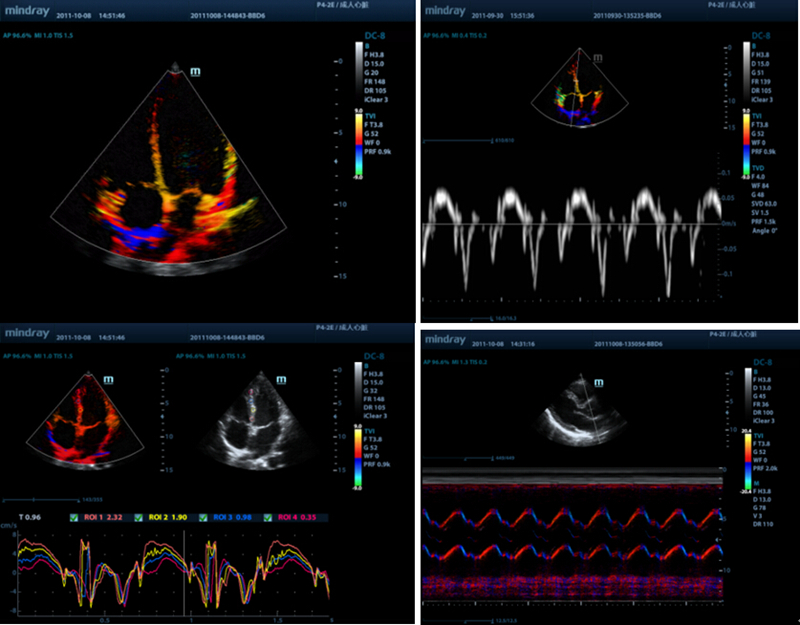

Free Xros CM?

Voor nauwkeurige evaluatie van myocardbeweging in verschillende fasen, en tegelijk bepaling van myocardiale synchronisatie. Hoge framesnelheid biedt nauwkeurige resultaten:

TDI

Met Tissue Doppler Imaging kunt u de plaatselijke myocardbeweging en -functie kwantitatief evalueren met volledige TDI-modi voor snellere en directe diagnoses.

Stressecho

Voor nauwkeurige meting van de myocardfunctie als reactie op externe stress of medicatie

AutoEF

Een intelligente manier om 2D-echoclips zo te analyseren dat diastole/systoleframes automatisch worden herkend en EDV/ESV/EF-resultaten, enz. worden uitgevoerd via de Simpson-methode

Auto LV

Eenvoudige meetprocedure voor linkerventrikel, verbeterd door automatische traceerfunctionaliteit en eenvoudige handmatige correctie